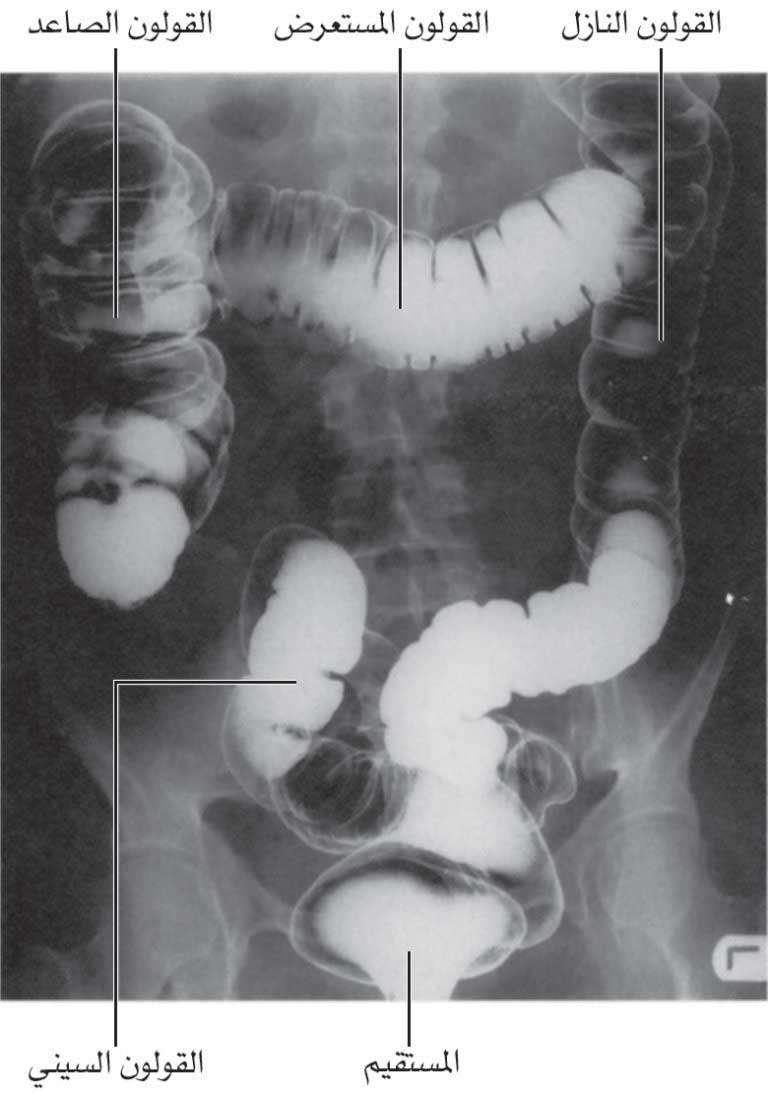

يبدأ المعي الغليظ من الحفرة الحرقفية اليمنى مشكلاً الأعور مع الزائدة الملحقة بالأعور، ثم يتواصل نحو الأعلى مشكِّلاً القولون الصاعد الذي يصعد في الخاصرة اليمنى right flank والمراق الأيمن right hypochondrium. عندما يصل القولون الصاعد تحت الكبد ينثني نحو اليسار مشكلاً الانثناء القولوني الأيمن (الانثناء الكبدي أو الزاوية القولونية اليمنى)، ثم يجتاز البطن عرضياً مشكلاً القولون المستعرض حتى يصل المراق الأيسر؛ وهنا وتحت الطحال مباشرة ينثني المعي الغليظ نحو الأسفل مشكلاً الانثناء القولوني الأيسر (الانثناء الطحالي splenic flexure أو الزاوية القولونية اليسرى)، ويتواصل باسم القولون النازل (القولون الأيسر) الذي ينزل عبر الخاصرة اليسرى والحفرة الحرقفية اليسرى. يدخل المعي الغليظ بعدئذٍ في القسم العلوي من جوف الحوض مشكلاً القولون السيني sigmoid colon، ثم يتواصل على الجدار الخلفي لجوف الحوض مشكلاً المستقيم، قبل أن ينتهي مشكلاً القناة الشرجية.

![]() |

| الشكل (3) صورة شعاعية باستخدام الباريوم بظهر المعي الغليظ |

3- القولون: يمتد من الأعور باتجاه الأعلى، وهو يتألف من القولون الصاعد والقولون المستعرض والقولون النازل والقولون السيني. يتوضع القولون المستعرض والقولون السيني ضمن الصفاق، ويرتبطان بجدار البطن الخلفي بوساطة مسراق خاص بكل منهما.